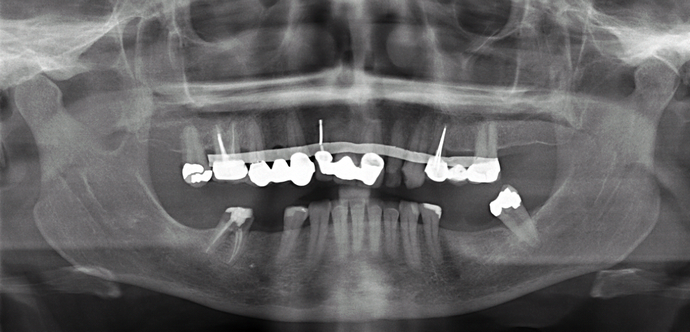

This patient had spent her whole life at the dentist’s office and had spent thousands of dollars on fillings, crowns, root canals, bridges, remake of bridges all of which eventually were failing and she was referred to Dr Bidra for comprehensive permanent solutions. Dr. Bidra determined that most of her lower teeth could be saved but her upper teeth needed a permanent All on 4 bridge which was all accomplished in 1 day without any bone grafting! The bottom jaw received just 2 implants after removal of diseased teeth.

Procedures : extractions, implants, All on 4 , Teeth in a day, no bone grafting and full mouth reconstruction with monolithic zirconia bridges.